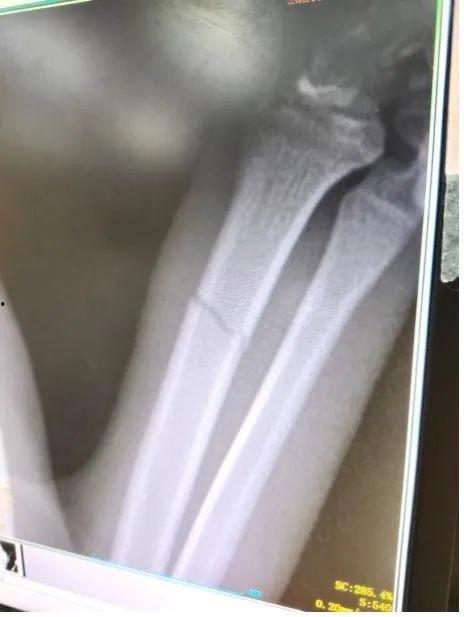

2022年,娱乐圈的明星们似乎特别容易遭遇骨折的“硬伤”。从影视演员到歌手,从体育明星到网红,骨折成了他们职业生涯中的一大挑战。那么,这些明星们究竟是如何受伤的呢?

影视演员篇:伤痛背后的坚持

1. 赵丽颖骨折,产后复出之路坎坷

2022年,赵丽颖产后复出之路可谓一波三折。在拍摄某部电视剧时,赵丽颖不幸遭遇骨折,这让粉丝们心疼不已。坚强的她并没有因此放弃,在经历了漫长的康复期后,她依然坚持出现在荧幕上,为观众带来了精彩的表演。